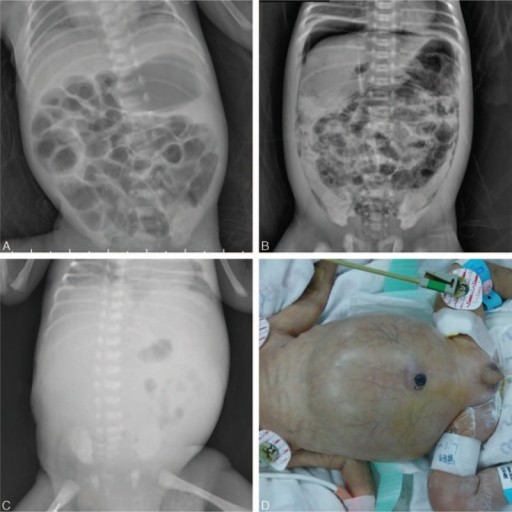

Saat anamnesis keluhan utama adanya distensi abdomen, masalah pemberian minum, muntah, residu lambung tinggi, diare, dan tinja berdarah. Dari pemeriksaan fisik ditemukan tanda abnormal di daerah abdomen, yaitu distensi, eritema dan indurasi dinding, massa terlokalisir yang persisten, asites, atau tanda ileus.

Gangguan sistemik yang menyertai seperti dispnea, bradikardi, letargi, oliguria, asidosis, bahkan kondisi syok. Pemeriksaan penunjang yang dapat mendukung diagnosis NEC adalah dan pencitraan abdomen dan pemeriksaan laboratorium darah.[1-4]